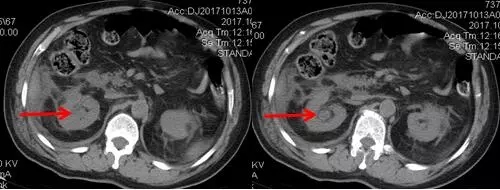

術(shù)后CT,箭頭所指為腎結(jié)石被徹底清除

三日后,曾奶奶病情逐漸穩(wěn)定,各項感染指標逐漸恢復正常,復查CT顯示腎結(jié)石已經(jīng)被完全清除,現(xiàn)已康復出院。就此,困擾曾奶奶多年,反復感染差點致命的腎結(jié)石頑疾被徹底治愈。曾奶奶全家人對于愛康醫(yī)院泌尿外科專家高超的碎石取石手術(shù)技藝更是贊許有加,對泌尿外科團隊的工作給予衷心感謝和高度評價。